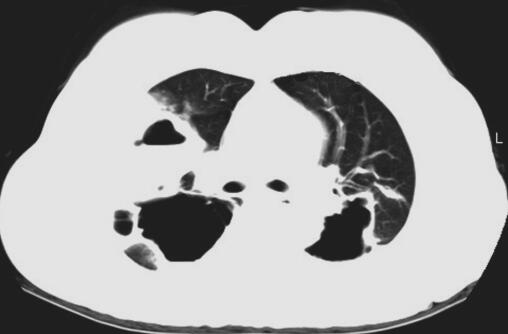

患者入院后考虑肺囊肿继发感染,给予抗感染治疗,完善相关检查,血常规:WBC 11.19×109/L,N% 68.90%;肺肿瘤标志物:CEA 2.46ng/ml,CYFRA 4.34ng/ml,NSE 9.38ng/ml;胸部CT示双肺气液囊肿并感染可能(图1);绒毛膜促性腺激素(β)HCG-BETA 5.48mIU/ml;电子支气管镜镜检未见异常;电子支气管镜肺活检病理示:子宫胎盘部位滋养细胞肿瘤肺转移。

图1 肺CT示双肺气液囊肿并感染可能

此例患者胸部CT提示双侧肺野多发液气囊性改变,考虑与滋养细胞在肺内破坏血管壁进入肺泡,使周围组织发生炎性浸润、出血、水肿,各肺泡病变融合成团,中心坏死,形成囊肿样改变,同时滋养细胞进入呼吸性细支气管为中心的细支气管周围组织发生炎性浸润,使呼吸性细支气管狭窄、闭塞,当囊肿内黏液潴留过多,或继发化脓性感染时,囊腔易与呼吸性细支气管穿透,形成单向性活瓣样通气,从而导致囊腔内压力不断升高,形成张力性液气囊肿改变。